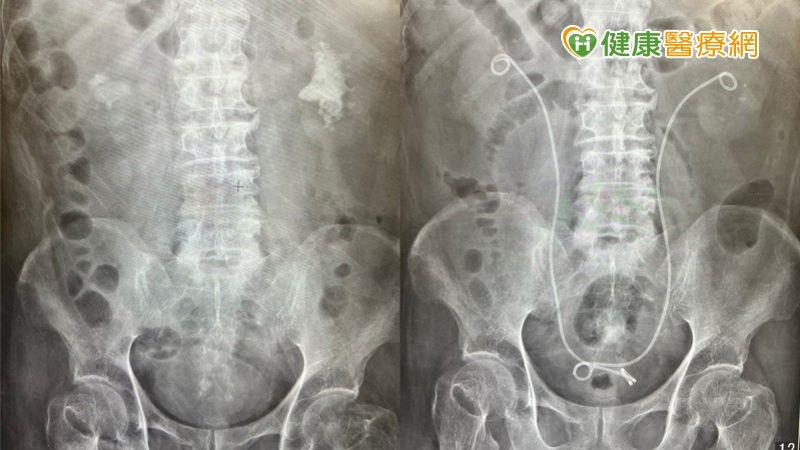

南投一名65歲男性長期有腎結石狀況,也曾在外院接受體外震波治療,依舊無法將石頭排乾淨。由於疫情中斷定期檢查,血尿狀況頻繁發生後,就醫才發現結石已有8公分之大,為了降低對腎臟傷害及手術併發症,後續病人接受「新式Mini軟式輸尿管鏡內視鏡手術 (Mini RIRS)」治療,即便是8公分巨無霸的腎結石也一次吸除乾淨,並且沒有任何傷口。

新式Mini軟式管徑7.5Fr相較於一般軟鏡管徑9Fr大幅減少30%,降低輸尿管損傷率,且有效降低手術併發症及提升成功率。新式Mini軟式輸尿管鏡內視鏡手術,又稱為吸石雙嬌,「管徑7.5Fr Mini軟式輸尿管鏡搭配可彎曲專利吸引導管」有別於以往軟式輸尿管鏡手術,無須使用取石網取石,邊打邊吸,縮短手術時間,提升清石效率!

● 新式Mini軟式輸尿管鏡內視鏡手術 (Mini RIRS):又稱為吸石雙嬌,管徑7.5Fr Mini軟式輸尿管鏡&可彎曲專利吸引導管,擊碎結石效果佳,跟一般軟鏡相比,直徑大幅小於30%,可以穿梭在較細的腎盞及漏斗之間,邊打結石邊吸石,無需使用取石網取石,病患也無須擔心石頭是否有完全排出,目前仍屬於自費手術,健保並未納入給付。

黃煒軒醫師進一步說明,管徑7.5Fr Mini 軟式輸尿管內視鏡進入位置為尿道,由人體天生擁有的天然管道進入、進行腎結石治療,不需額外製造新傷口。所使用的「可彎曲專利吸引導管」能彎曲180度,並且深入下腎盞,藉由反覆抽吸灌注,可以有效控制術中腎內壓,減少熱傷害以及術後感染風險,也可以大幅降低輸尿管損傷的風險。因為不必開刀、沒有傷口,特別適合年紀較大、共病史多、服用抗凝血劑的患者,除了能減少恢復時間,同時也較安全。